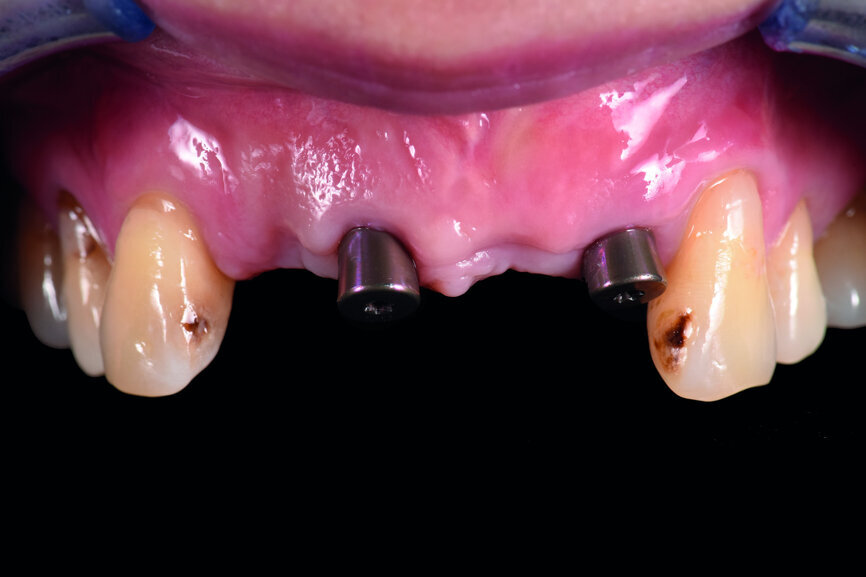

A 40-year-old female patient had sustained trauma to her anterior teeth caused by accidental syncope three weeks before. The clinical examination found that tooth #11 had been luxated; the crowns of teeth #12 and 21 had fractured, with the residual margin extending 3–5 mm below the gingiva and the teeth affected by Grade III mobility; and the crown of tooth #22 had fractured, with the residual margin at gingival level. There were no obvious abnormalities in the remaining teeth (Figs. 1–4). After excluding major systemic diseases, it was decided that she required fixed implant restoration with high demands regarding aesthetics and function.

Fig. 1: Pre-op frontal view of the anterior teeth.

Teeth #12, 21 and 22 were extracted. Tooth #11 underwent early implantation and tooth #22 immediate implantation with GBR (Figs. 5 & 6). After three months of healing, osseointegration had taken place. An implant level impression was taken for fabricating a provisional bridge supported by temporary abutments for teeth #12–22. The technician modified the shape of the artificial gingiva on the model in order to form the proper gingival curve and emergence profile, then finished the provisional bridge, while the dentist modified the gingival shape using an olive-shaped bur intraorally (Figs. 7–18).